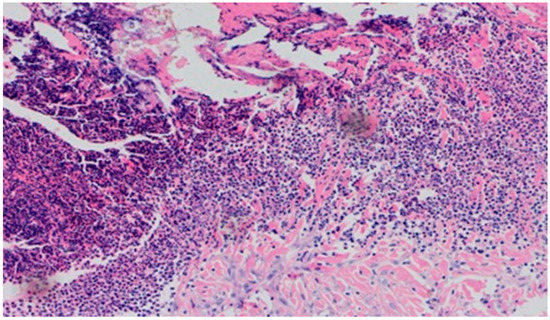

On day 5 of the experiment, slight differences in the wound healing process were observed. Inflammation was present in all wounds and the surrounding tissues, however, with a different intensity, type and depth of infiltration. In group D1, treated with the 1% propolis ointment, there was a moderately dense granulocytic infiltration reaching the dermis. Wounds in group D2, treated with the 1% nanosilver ointment, were characterized by a granulocytic infiltration with a low density and depth of infiltration reaching the dermis. In wounds treated with a mixture of 1% propolis and 1% nanosilver, there was a large granulocytic inflammatory infiltration reaching the depth of the adipose tissue. Wounds treated with sulfathiazole were characterized by a small, mixed infiltration reaching the dermis. On day 5 of the treatment, all wounds from the experimental and control groups did not show any epidermization features. Superficial necrosis was low in the experimental groups and a high degree of necrosis was observed in the sulfathiazole-treated control group. The histopathological findings from day 5 are presented in Table 8 and Figure 13 and Figure 14.

Figure 13. Granulocytic inflammatory infiltration on the border of the dermis and subcutaneous tissue (100×, H-E), in the wound treated with the ointment with 1% propolis and 1% nanosilver, on day 5.